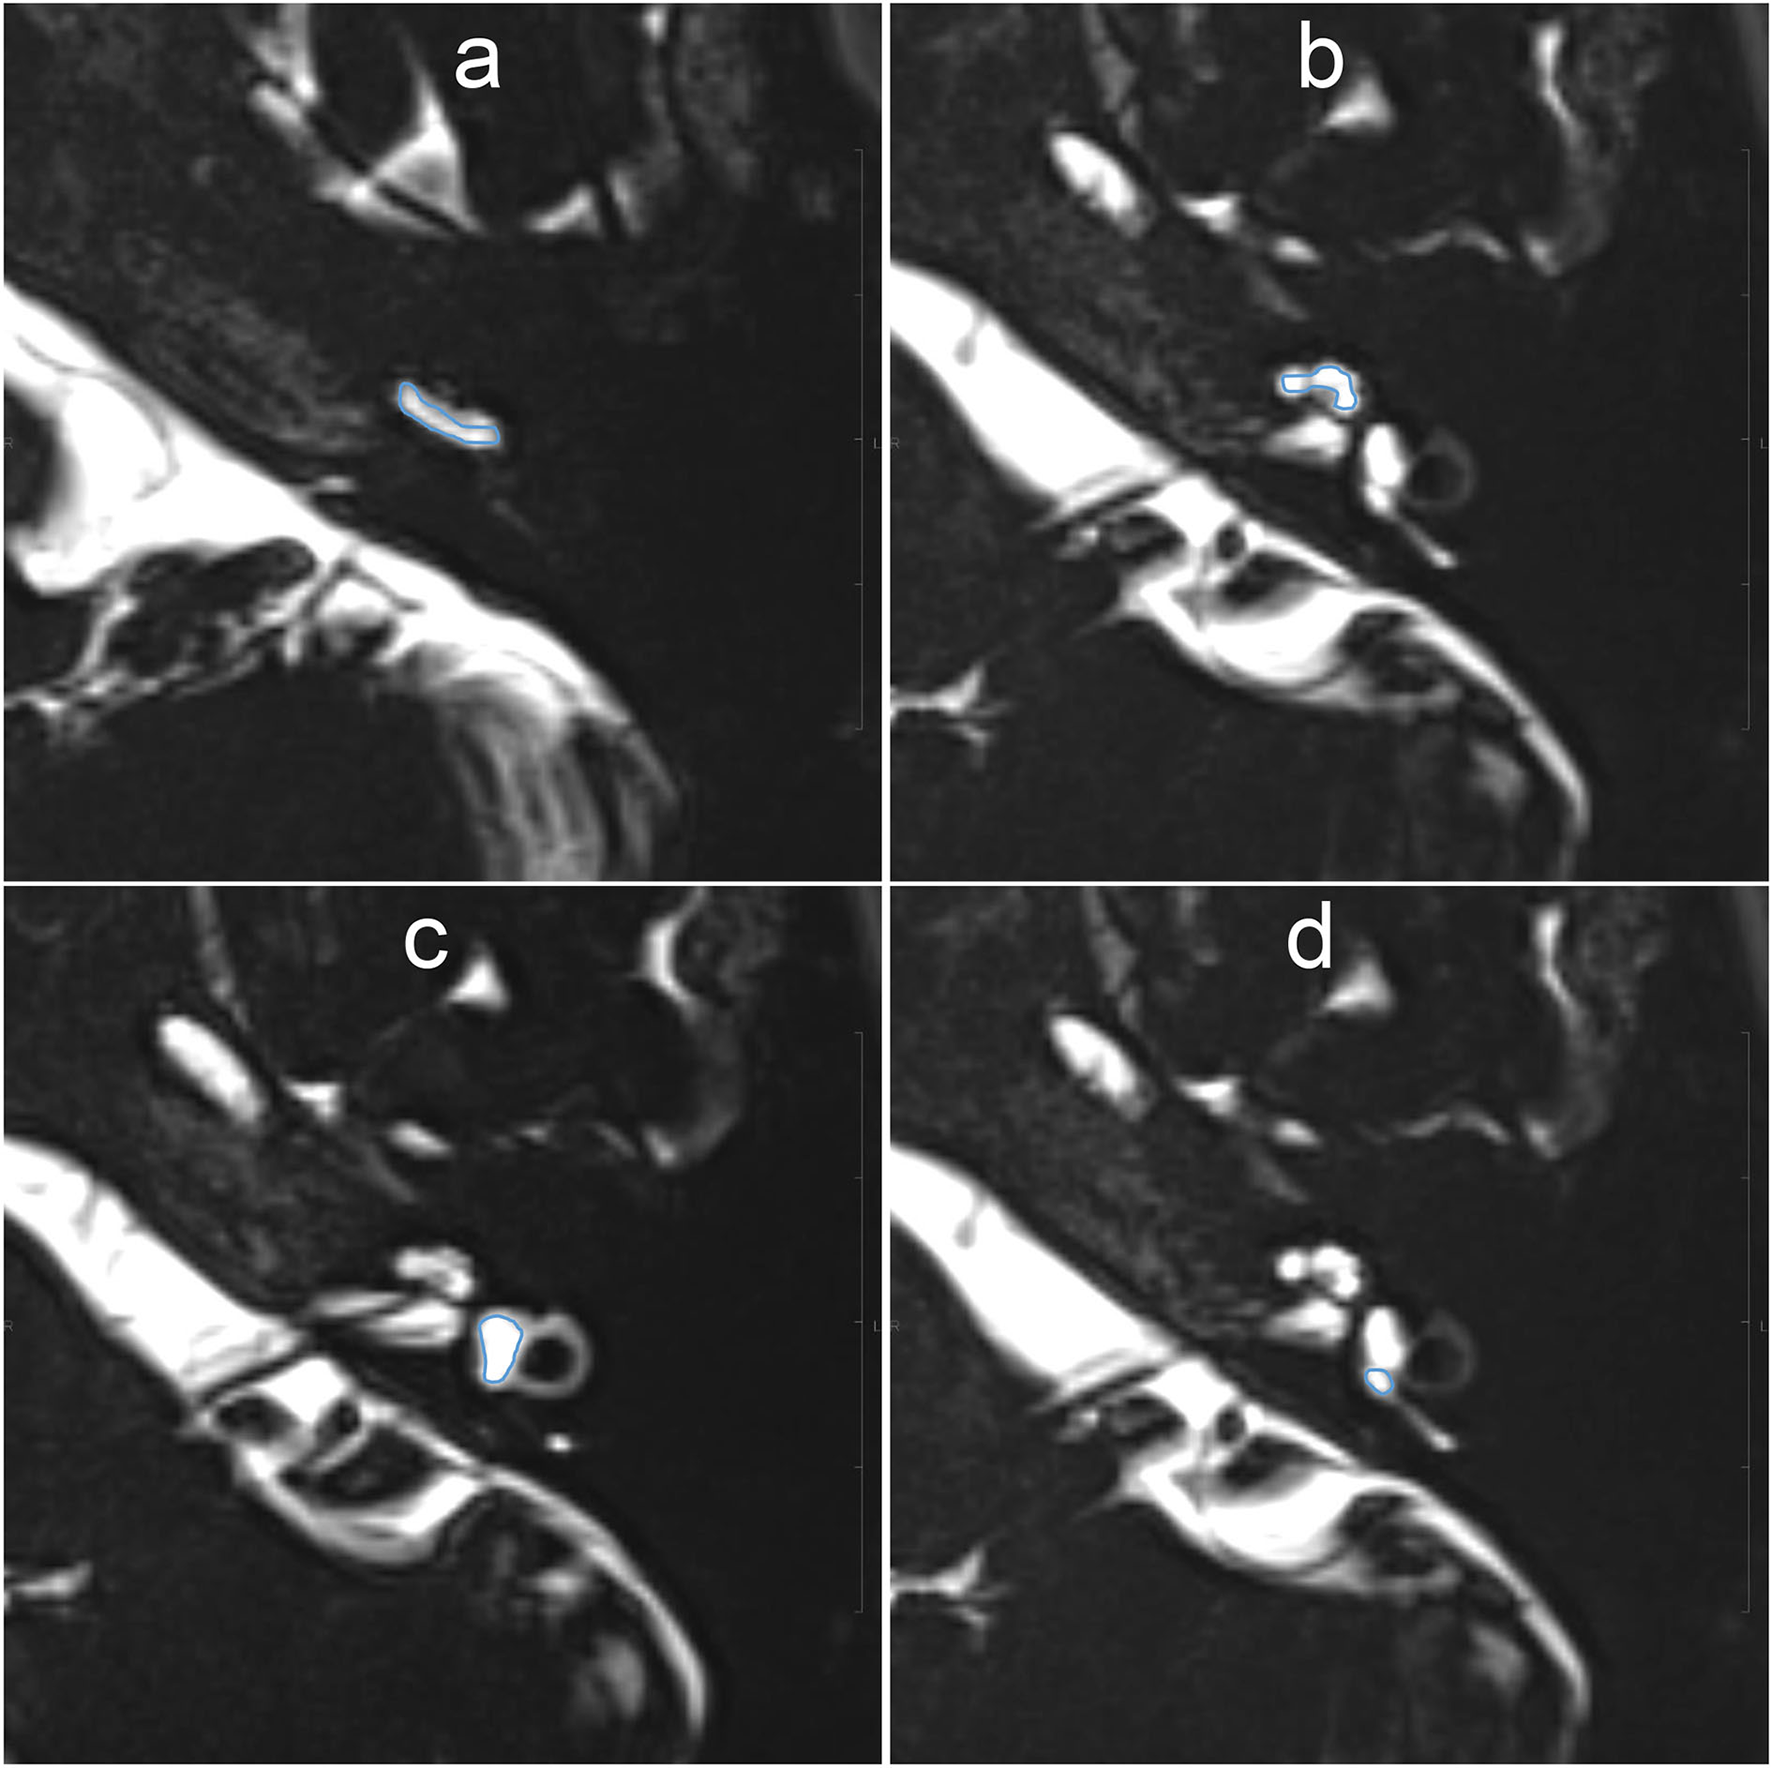

For quantitative evaluation, the SIR between the signals of the injected left side and the non-injected right side was measured on MR images with a TE of 3,200 ms. The ROIs were drawn manually on the MR images with a TE of 540 ms, and were copied and pasted onto MR images with a TE of 3,200 ms and onto MR images taken during another time phase (Figure 3). If motion was detected between the scans, fine adjustments were made manually. Using the signal value of the ROI for the right side as a control, each SIR was calculated as the signal intensity of the ROI in the left side divided by that in the right ear. The ROIs were placed using a PACS viewer (Rapid-eye Core, Canon Medical Systems, Tochigi, Japan) by a single observer with 15 years of experience in the evaluation of inner ear MRI.

Figure 3

Example images for setting of the region of interest (ROI) on MR images with an echo time (TE) of 540 ms. The scala tympani of the basal turn of the cochlea (a), whole apical–middle turn (b), vestibule (c), and the ampulla of the posterior semicircular canal (d) appeared contoured. The ROIs were then copied onto the other TE images. Each signal–intensity ratio was calculated using the signal value of the contralateral inner ear as a control.